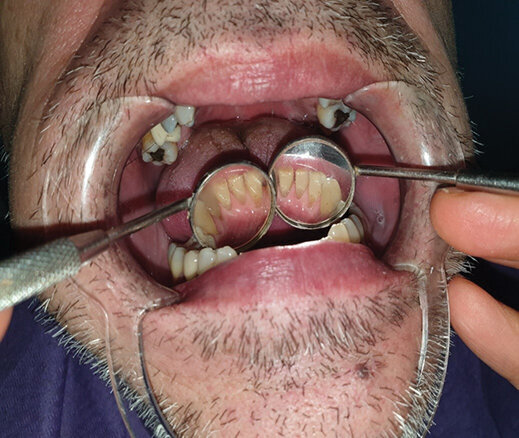

Pacijent B pušač pri prijemu. Estetski neprihvatljive pušačke pigmentacije na svim površinama zuba, naročito onim u estetskoj zoni, direktno izloženim glavnoj struji duvanskog dima. Zubni kamenac i meke naslage ukazuju na nizak nivo oralne higijene. Uočava se i prebojenost kompozitnih aproksimalnih plombi gornjih prednjih zuba. Slabije izražene melanogene pigmentacije desni. Jezik pacijenta takođe je obložen (Sl. 2.0).

Sl. 2.0: Pacijent B, pušač pri prijemu